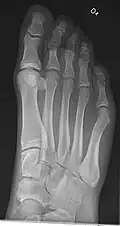

• Hand - DP and Oblique

• Fingers - DP and Lateral

• Thumb - AP and Lateral

• Foot / Toes - Dorsoplantar, Oblique and Lateral.[19]